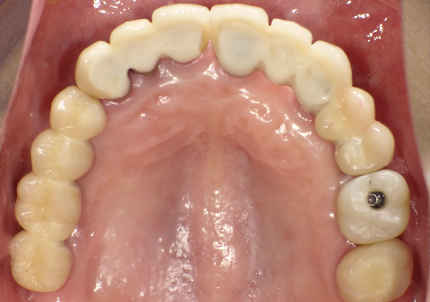

1.初診時(2015年6月)

2.最終補填物装着(2018年3月)

3.術後8年経過(2023年3月)

術後8年経過良好

2015年6月初診時レントゲン

2023年3月レントゲン 経過良好